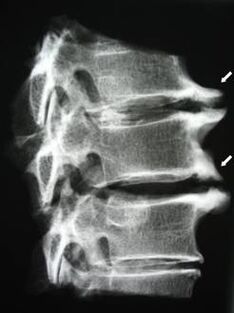

Sākotnējās stadijās osteohondrozi atklāj, izmantojot MRI. Vēlāk patoloģiju var diagnosticēt, izmantojot radiogrāfiju. Uz mugurkaula kakla daļas rentgenogrammām kļūst pamanāms attāluma samazināšanās starp skriemeļiem, patoloģiskas izmaiņas fasešu locītavās un osteofitoze.

| Dzemdes kakla osteohondroze | Patoloģisku izmaiņu parādīšanās vienā vai vairākos mugurkaula kustības segmentos. Mugurkaula mobilitātes traucējumi, miofasciālu sāpju sindromu attīstība un mugurkaula sakņu saspiešana | Sāpes, parestēzijas un kustību traucējumi dzemdes kakla rajonā, kas izplatās uz pakauša un augšējo ekstremitāšu daļu. Mugurkaula raksturīgo izmaiņu noteikšana MRI un rentgenogrammās (osteofīti, samazināts attālums starp skriemeļiem, starpskriemeļu locītavu bojājumu pazīmes) |